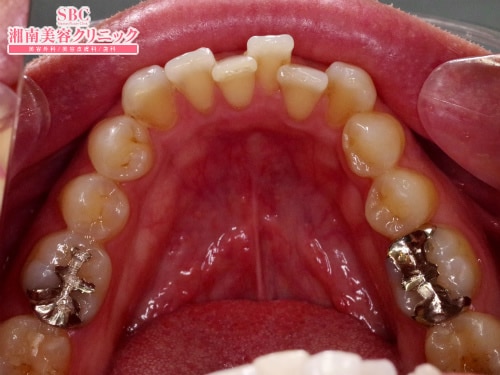

施術前

湘南歯科グループ唯一の技術指導医審美・美容歯科経験西日本No.1歯科西エリアマネージングドクター経験・診断・技術に基づいた本物の施術をご提供致します。マウスピース矯正=インビザラインGOの症例です。術前のガタつきの目立つ前歯。この歯並びをマウスピースを1日20時間以上装着する事で改善。ガタつき整いました。

マウスピース矯正=インビザラインGOの症例です。

術前のガタつきの目立つ前歯。

この歯並びをマウスピースを1日20時間以上装着する事で改善。

ガタつき整いました。